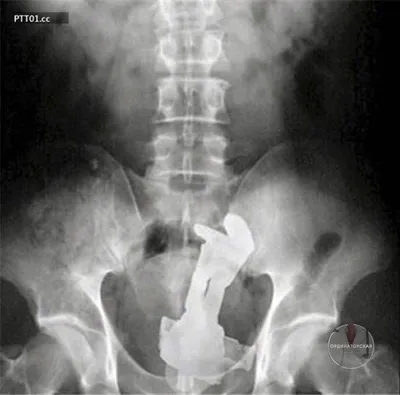

Самые странные предметы, которые проявлял рентген в людях 😨

11 мар. 2026 г.

4.4k 61 28

Посмотрите на этот полный боли снимок. Этот пациент уже не придумывал истории про то, как случайно упал на флакон духов. Ему было настолько больно, что он не мог говорить. Дело в том, что крышка о

4 мар. 2026 г.

4.2k 96 33